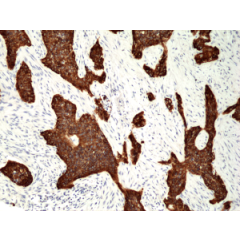

anti-Cytokeratin-8 (human), Rabbit Monoclonal (RM266)

anti-Cytokeratin-8 (human), Rabbit Monoclonal (RM266)

REV-31-1148-00 REV-31-1148-00-R100 100 µl CHF 468.00